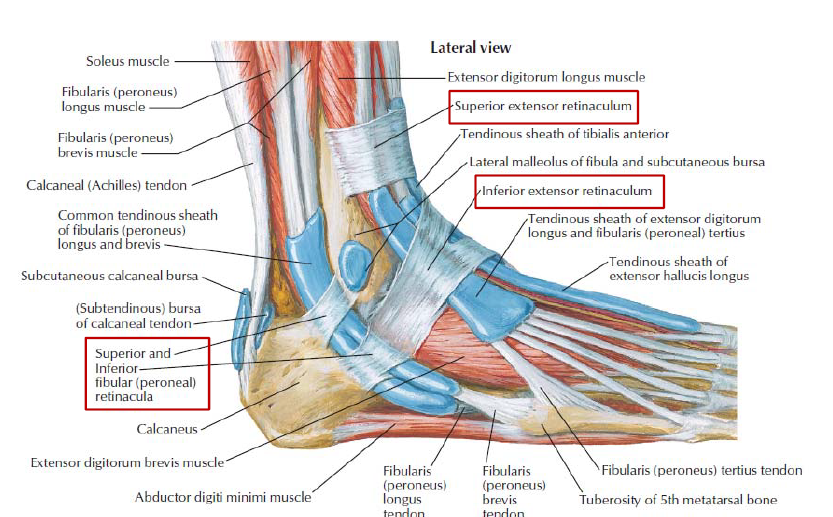

common fibular n. 傳到 Fibularis longus下再分支

Muscle

由內而外(Extensor retinaculum之下)